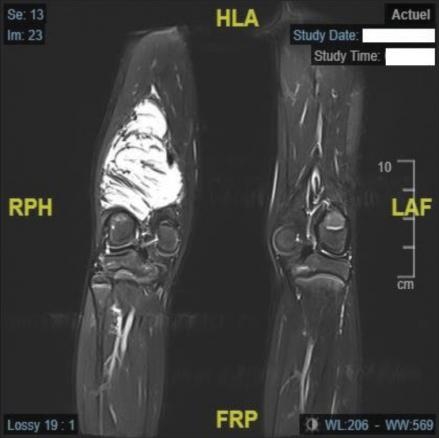

L’IRM confirme l’existence d’une masse tissulaire avec contingent graisseux refoulant les structures de voisinage (figures ).

L’IRM confirme l’existence d’une masse tissulaire avec contingent graisseux refoulant les structures de voisinage (

L’IRM est l’examen d’imagerie de choix pour préciser la localisation et les rapports de la lésion. Si elles sont réalisées, la radiographie ne montre pas de lyse osseuse et l’échographie met en évidence une masse hétérogène à contenu graisseux.